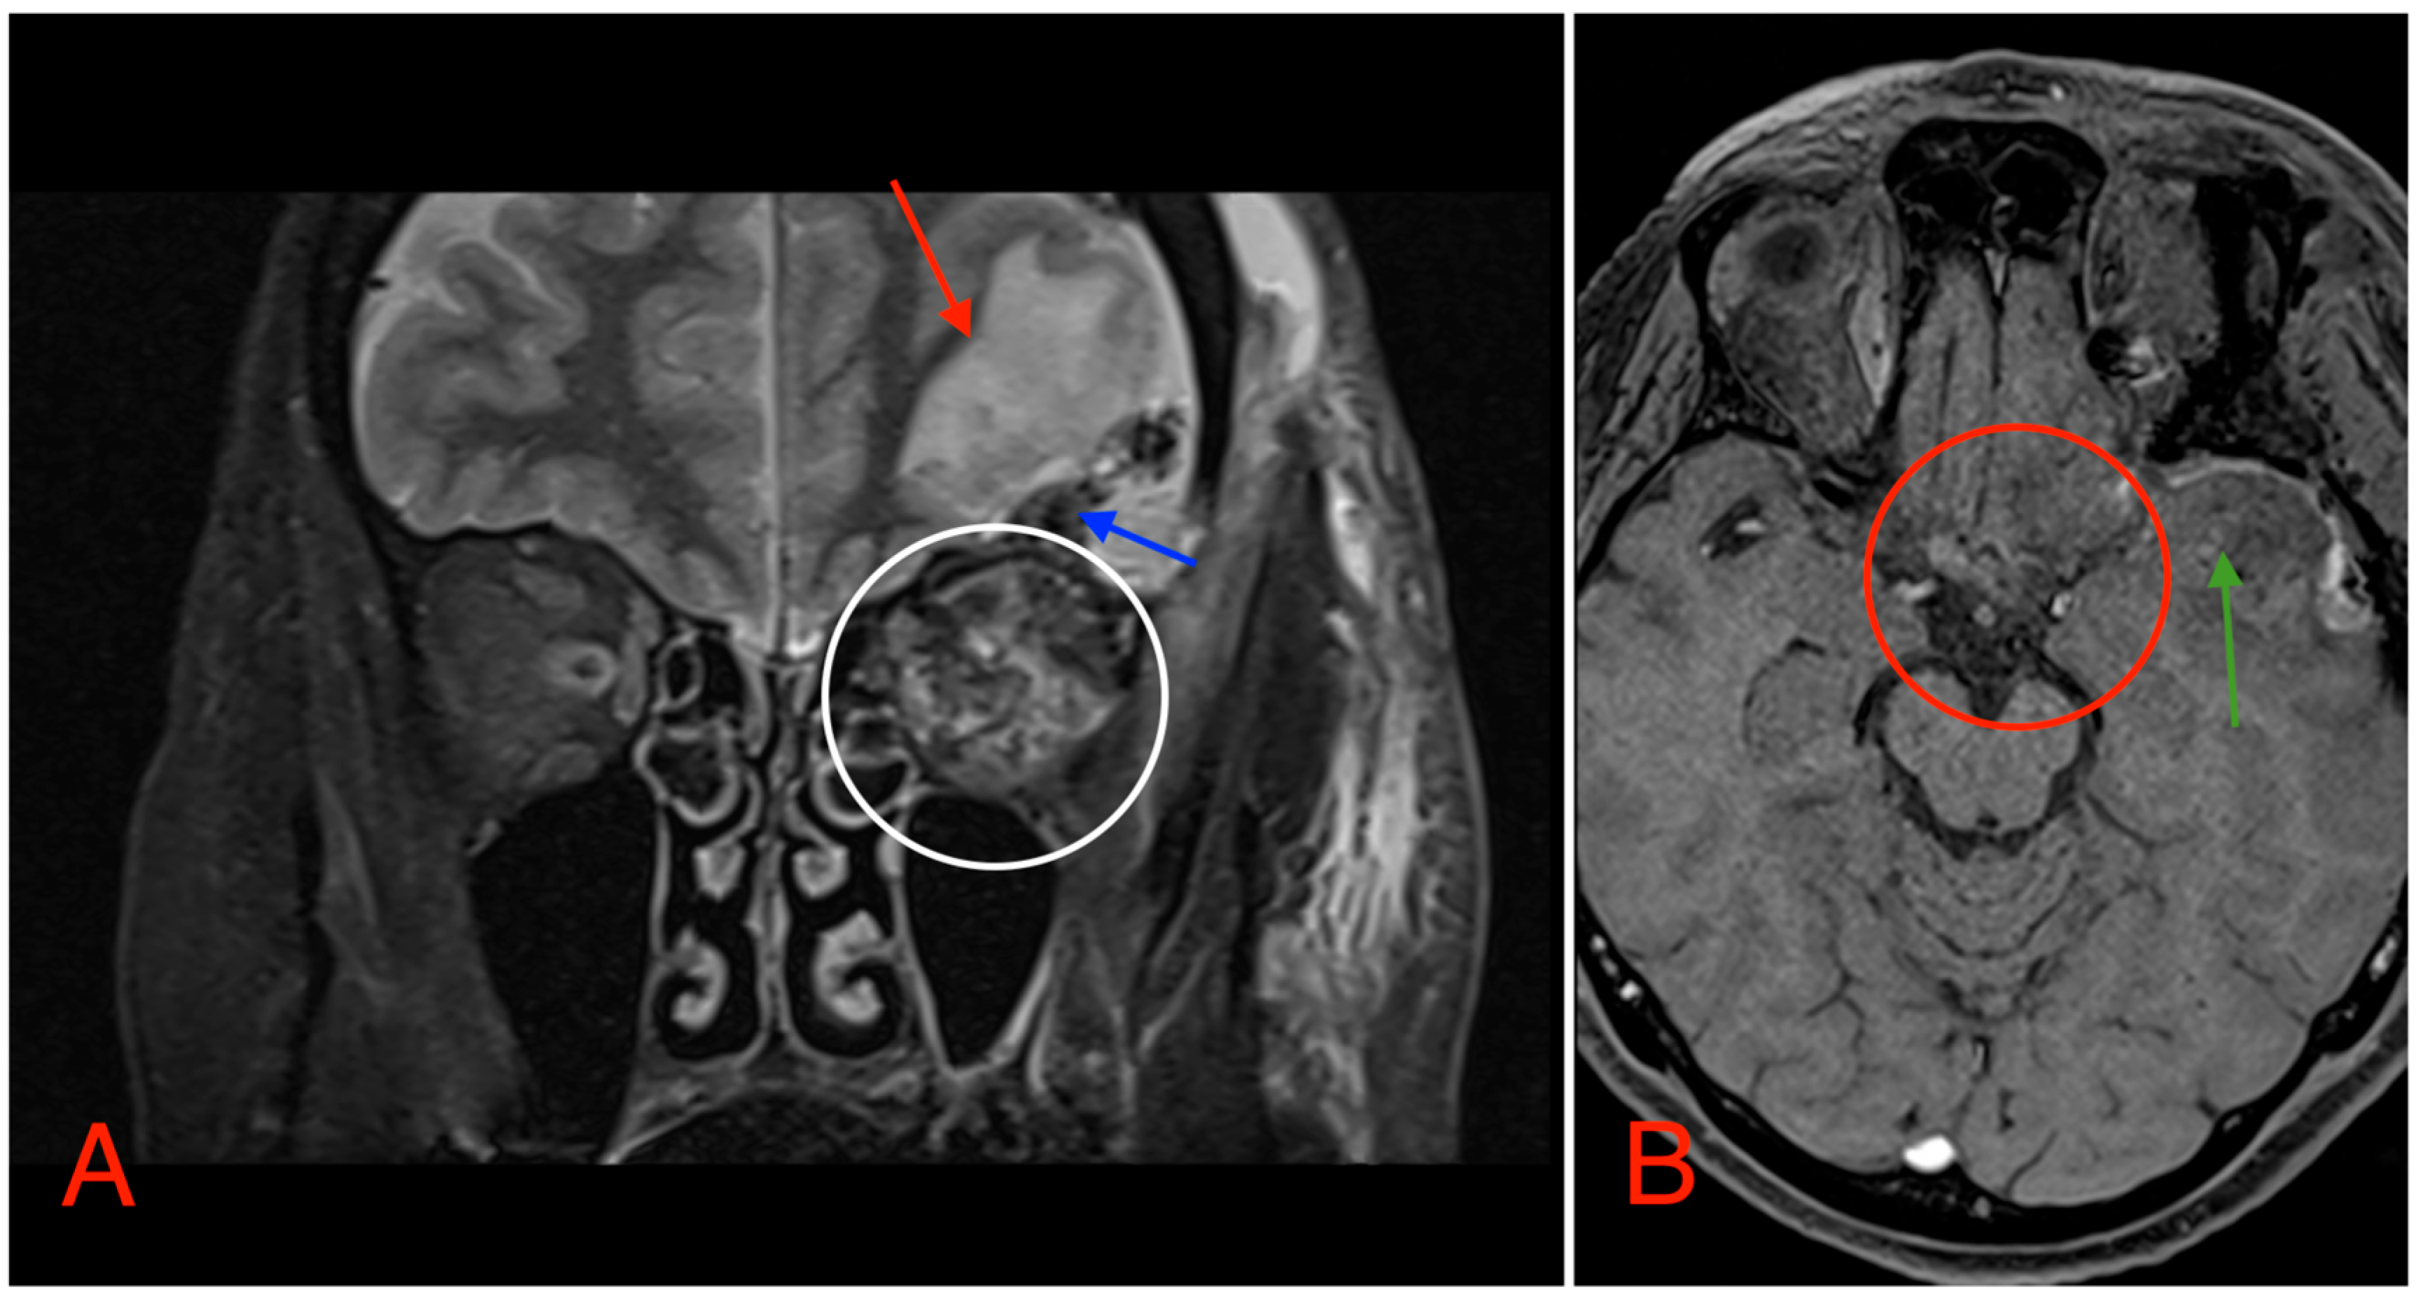

The CT scan revealed a pathological mass in the intraconal space, ~1.5 cm × 2.5 cm × 1.5 cm, which occupied most of the orbit. Noticeable thinning and depression of the rectus muscles of the eye were also noted (Figure 3). A cranial contrast enhanced MRI was conducted the following month, revealing an entirely altered optic nerve affecting the retrobulbar, prechiasmal, and optic chiasm level. A pathological, smoothly contoured mass with cystic changes was described and measured about 5.2 cm × 2.0 cm × 1.9 cm. Greater peripheral contrast accumulation in the pathological tissue extended along the optic chiasm and relatively close to the frontal lobe’s straight gyrus. The pathological mass also extended relatively close to the A1 segment of the anterior cerebral artery and stretched in the direction of the pituitary gland. A lateral depression of the extraocular muscles was also noted (Figure 4). The contrast-enhancing component of the tumor on diffusion-weighted imaging (DWI) sequence showed a restricted diffusion at an apparent diffusion coefficient (ADC) value of 1500 × 10−6 mm2/s, with a b value of 1000 s/mm2. A high T2 signal intensity was also noted.

Figure 4. (A) MRI image, T1 VIBE fat-saturated post-gadolinium image sequence, axial plane, demonstrating an intraconal tumor which most likely originated from the optic nerve with intraconal and intracranial involvement, cystic changes (red arrows), and contrast enhancement (white circle). The intracranial compartment involves the optic chiasm with a mass effect on the surrounding structures and large blood vessels (red circle). (B) MRI image, T2 TSE Dixon sequence, coronal plane, showing both solid and cystic parts of the optic nerve tumor with a retrobulbar segment mass effect and extraocular muscle suppression (green circle).

Postoperative head MRI showed partial resection of the left optic nerve. Residual tumor tissue and edema were noted in the left retrobulbar space, extending into the left prechiasmal space and into the left side of the optic chiasm (Figure 8).

Figure 8. (A) MRI image, T2 TSE STRI sequence, of the aftermath of the left-sided pterional craniotomy, showing postsurgical edema (red arrow) with a small hemorrhagic component (blue arrow). Postsurgical changes in the intraconal space can also be noted, showing an edema and a hemorrhage (white circle). (B) MRI image, T1 vibe post-gadolinium image sequence, showing postsurgical changes in the region of the optic chiasm with partial (subtotal) tumor resection (red circle). Local brain edema with hemorrhagic component (green arrow) can also be noted.